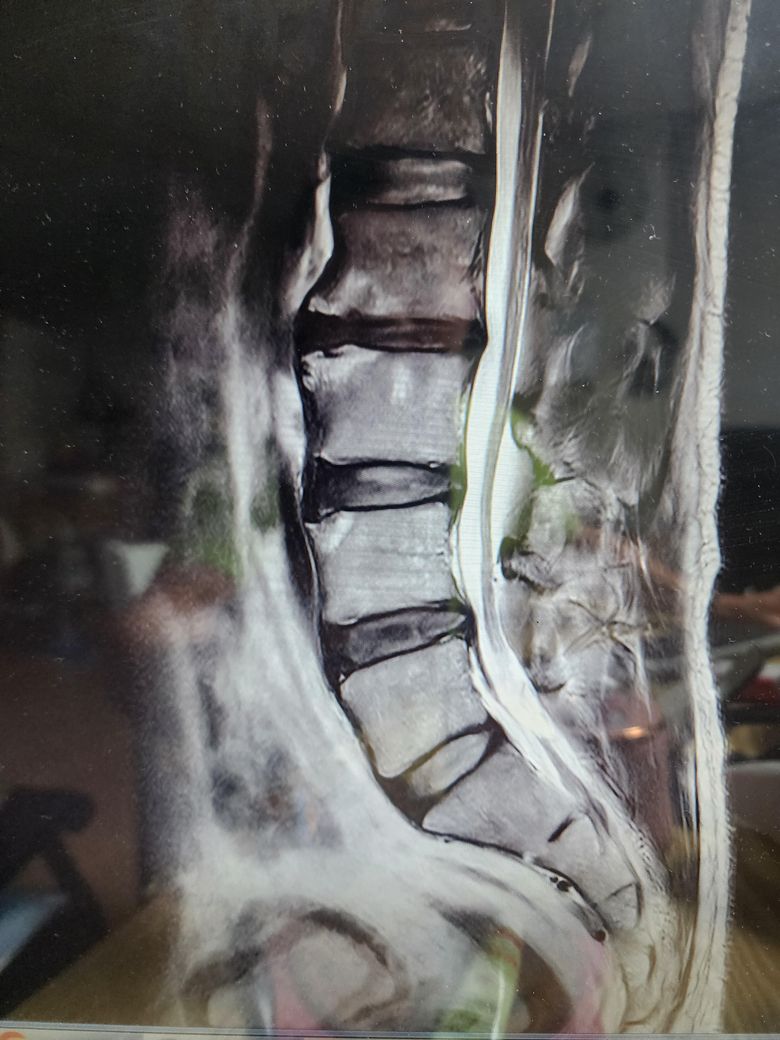

• 3번 째 사진

보여주신 MRI 상에는 척추관 협착증은 전혀 보이지 않습니다.

아래 첫번째 그림에 보시는것과 같이 B에서 보이듯이 검정색 신경뿌리 주변의 하얀색 뇌척수액이 공간 없이 비좁아지는 정도는 되어야 척추관 협착증이라고 이야기할 수 있을텐데 보여주신 MRI 에는 이런 모습은 없습니다.

추간판 공간이 줄어들어있고, 디스크 증상처럼 돌출이나 퇴행적 변화가 관찰되는 것으로 생각되는데요, 결국에 수술적 치료를 하더라도 보존적인 치료법을 먼저 시행하여 경과를 살펴보고 차도가 없는 경우 수술을 고려하는 것이 많기 때문에 우선 보존적 치료가 가능한 경우라면 수술은 조금 더 나중에 고려를 해보시는 것도 좋겠습니다. 수술을 고려중이신 경우에는 가능한 여러 전문의들의 의견을 들어보시는 것도 좋은 방법이 될 수 있겠습니다.